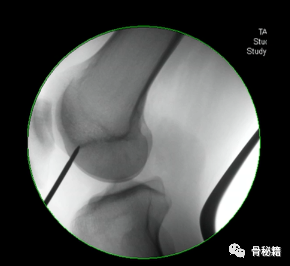

他在正侧位的透视位置我们可以看到位于髓腔中心的延长线上

对于股骨远端来说,主要是从布鲁门萨线进钉

5、钉子的深度。逆行髓内钉的最佳深度是布鲁门萨线的顶点位置,正位居中